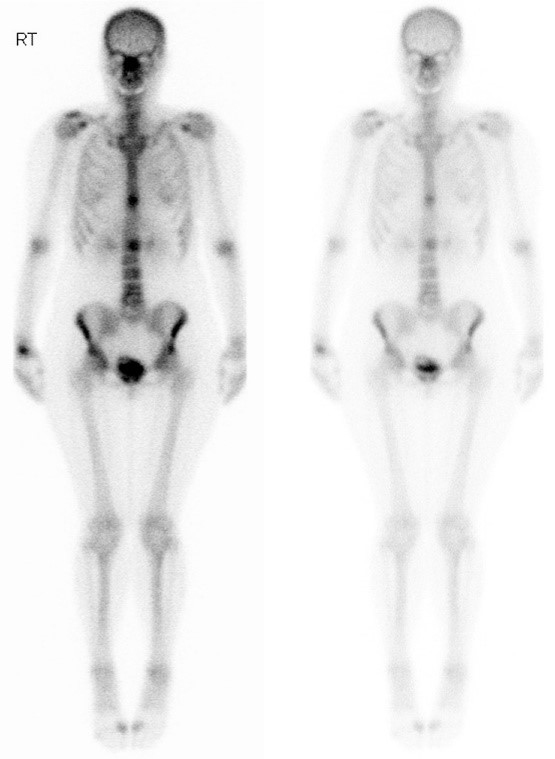

Vous avez fait réaliser une scintigraphie osseuse qui montre l’aspect suivant : Le scanner TAP confirme les localisations osseuses exclusives, hormis un nodule pulmonaire lobaire supérieur droit. L’IRM confirme l’attente de L2 et T10, sans risque neurologique immédiat. La patiente est correctement soulagée par ses morphiniques.

Question 12 - Concernant l’examen ci-dessus et la prise en charge que vous proposez :

Il existe en effet un hypermétabolisme bilatéral en regard des ailes iliaques.

Il s’agit de la vessie, et du produit de contraste accumulé à l’intérieur.

La choline est utilisée dans les TEP-TDM des cancers de la prostate.

Une scintigraphie osseuse nécessite l’injection de technétium 99, à la différence d’un TEP-TDM qui nécessite l’injection de 18-FDG.

La scintigraphie osseuse est un examen simple et parfois plus accessible qu’un TEP-TDM. Elle repose sur l’injection de bisphosphonates marqués au technétium 99, qui se fixe donc dans les zones où l’activité ostéoclastique est importante, dont les métastases osseuses. Il est indispensable de réaliser une biopsie chez cette patiente : – le type est à repréciser à quinze ans du cancer du sein, chez une femme fumeuse avec un nodule pulmonaire… ; – même en cas de récidive de cancer du sein, certains cancers RH+ récidivent sous la forme de cancers triple négatifs et donc ne nécessitent pas les mêmes traitements.

La biopsie confirme la récidive métastatique d’un cancer du sein RH+, HER2-.